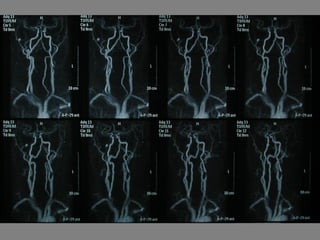

Un paciente de 75 años ingresó en el hospital debido a síntomas neurológicos como bradipsiquia, disartria y torpeza motora en las extremidades derechas que habían estado presentes durante las últimas 12 horas. Tenía antecedentes de fibrosis pulmonar e infección respiratoria reciente. El examen reveló disartria leve, paresia facial central derecha y claudicación en las extremidades derechas, lo que sugiere un posible ictus en el hemisferio izquierdo.